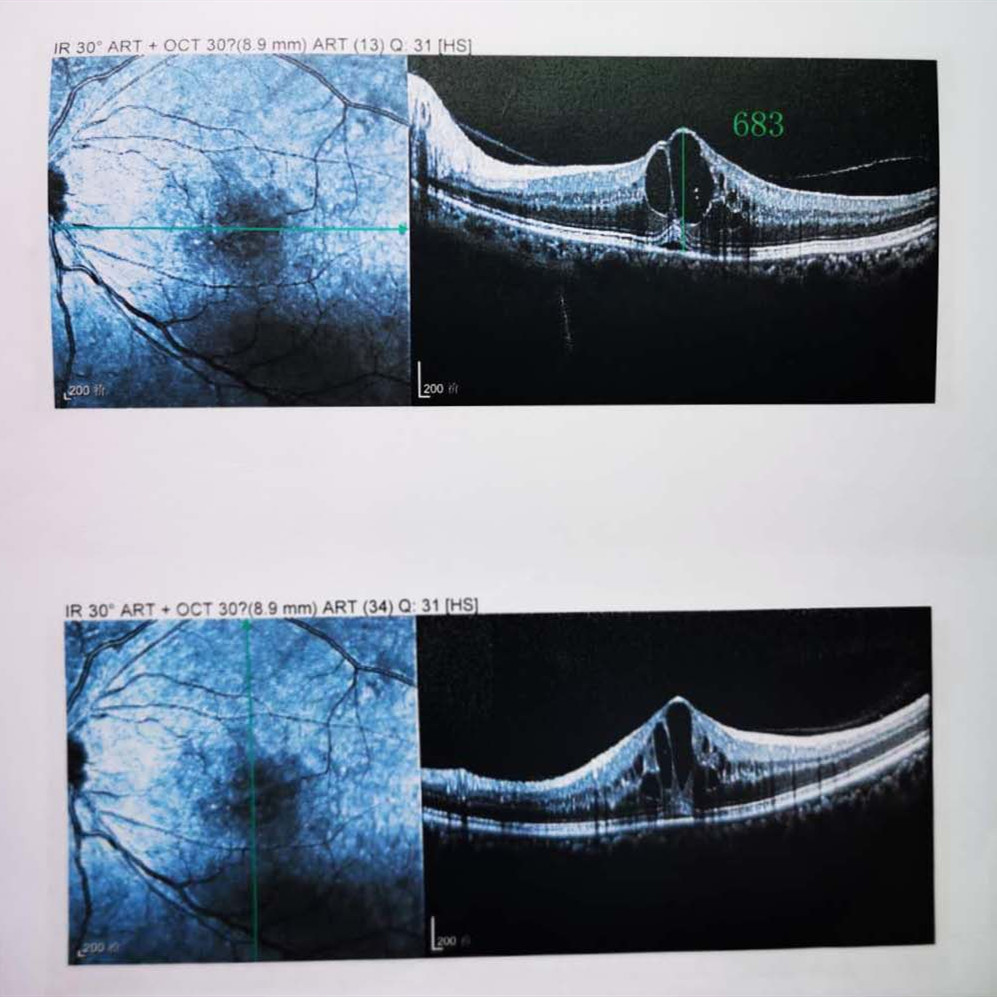

檢查結(jié)果顯示,武先生并沒有近視,右眼視力為1.0,但是左眼視力只有0.4,而且左眼視網(wǎng)膜各分支靜脈迂曲擴(kuò)張,全網(wǎng)膜面見火焰狀出血,黃斑區(qū)高度水腫、滲出,黃斑中心凹厚度約683um。

(武先生初次就診眼底OCT檢查圖)

而正常的矯正視力是1.0,黃斑中心凹厚度在200um左右。

“你這黃斑都腫到正常人的三四倍大了!”廈門眼科中心吳國基院長醫(yī)生告訴武先生,“你這是左眼視網(wǎng)膜中央靜脈阻塞伴黃斑水腫,你左眼的視力下降、看東西變形,是因?yàn)槟阕笱垡暰W(wǎng)膜的中央靜脈發(fā)生了阻塞、出血,導(dǎo)致眼底黃斑水腫了。”

那么,武先生的視力恢復(fù)情況如何呢?幸運(yùn)的是,經(jīng)過兩次玻璃體腔注藥術(shù),武先生左眼的黃斑水腫得到明顯改善,視力已經(jīng)恢復(fù)到0.8。

(武先生出院時眼底OCT檢查圖)